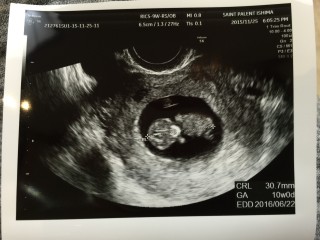

CRL30.7mm。 前回より10倍近く大きくなってて感動しました(>_<) 初めての妊娠で悪阻などで悩まされますが大きくなってるのを実感し頑張ろうと思えました!☆ みなさんの記載にも感動したり、励まされたりでいいサイトに出会いました^^ これからも覗きに来たいと思います☆

予定日が決まりました~! 赤ちゃんの大きさは27mm! 心臓が力強く動いてました! 先生から”順調だね”のお言葉をいただきホッとしました(*^^*) 3週間前は米粒みたいだったのに…赤ちゃんってすごい!!